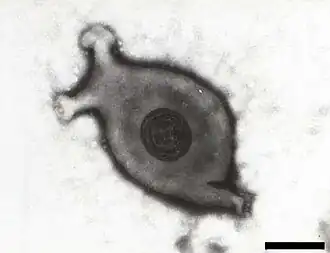

Die Zellformen der Mykoplasmen (Mollicutes) sind vielgestaltig (pleomorph), oft bläschenförmig (coccoid). Ihre Kolonien zeigen eine charakteristische Spiegeleiform.

Die zellwandlosen Mykoplasmen (Mollicutes), früher PPLO (pleuropneumonia-like organisms) genannt, vermehren sich durch Zweiteilung (binary fission) wie die anderen Bakterien oder durch einen Knospungsmechanismus. Fortlaufende Mikrofotografien von sich vermehrenden Mikrokulturen von verschiedenen Stämmen von Mykoplasmen, bakteriellen L-Formen und, als Kontrolle, einer Micrococcus-Art (als Beispiel für Zweiteilung) wiesen diese Vermehrungsweise nach.[9] Die lichtmikroskopischen Untersuchungen wurden elektronenmikroskopisch ergänzt.[10]